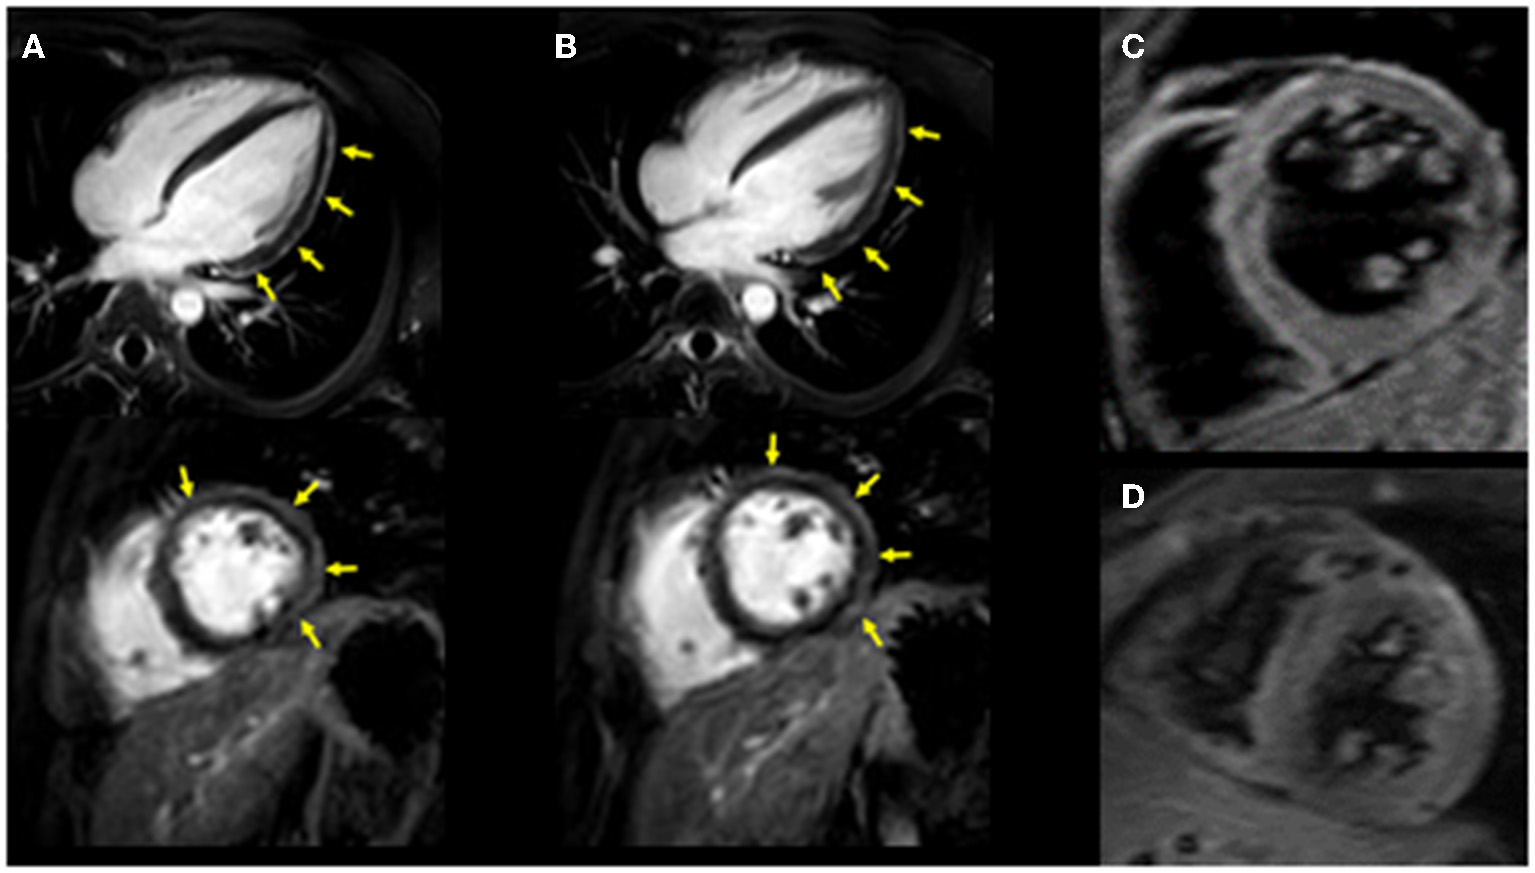

Figure 1

Cardiac MRI imaging. Diffuse late gadolinium enhancement at the epicardium was observed in both images. (A) Images obtained 3 years ago when he suffered from his previous myocarditis (top: long-axis view, bottom: short-axis view). (B) Images obtained during the current myocarditis episode associated with coronavirus disease-2019 (COVID-19) messenger RNA (mRNA) vaccination (top: long-axis view, bottom: short-axis view). T2-weighted MR images. (C) Image obtained 3 years ago when he suffered from his previous myocarditis episode. (D) Image obtained during the current myocarditis episode associated with COVID-19 mRNA vaccination.

The patient had a history of myocarditis (causative bacteria was Campylobacter) when he was 13 years old, which was treated with intravenous immunoglobulin (IVIG). His initial symptoms included fever, chest pain, and diarrhea. His maximum CK was 1,682 IU/L. Cardiac MRI revealed diffuse late gadolinium enhancement at the epicardium (Figure 1A). A cardiac biopsy was not performed. After the introduction of IVIG, his symptoms improved, for which he was discharged from the hospital without any apparent cardiac dysfunction assessed by echocardiography and myocardial scintigraphy. Enalapril 5 mg/day was introduced and was discontinued 1 year after this episode. He received regular follow-up at our institute, during which, his serum cardiac enzymes were assessed, and electrocardiography and echocardiography were performed. No signs of recurrence had been observed until his last visit 6 days before his second COVID-19 mRNA vaccination. Echocardiography revealed a normal left ventricular ejection fraction (LVEF = 75%), without other dilatations in any chambers, and his cardiac troponin T level was within the normal range (0.006 ng/ml) in his last visit (6 days before his second COVID-19 mRNA vaccination).

Upon admission to our hospital, the patient had blood pressure, heart rate, and body temperature of 135/65 mmHg, 97 bpm, and 37.3°C, respectively. Chest radiography showed no signs of cardiomegaly or pulmonary congestion. Blood tests revealed an elevation in white blood cells (9,560/μl) and C-reactive protein (4.44 mg/dl, normal range ≤0.3 mg/dl), together with elevations in cardiac enzymes, including CK (818 IU/L, normal range 62–287 IU/L), CK-MB (59 IU/L, normal range 2–21 IU/L), and cardiac troponin T (1.41 ng/ml, normal range ≤0.014 ng/ml). The N-terminal pro-brain natriuretic peptide (NT-pro BNP) level was also elevated (221.2 pg/ml, normal range ≤ 125 pg/ml). Electrocardiography revealed ST elevations in V2–V5 leads, whereas echocardiography revealed systolic dysfunction (LVEF = 55%) associated with left ventricular dilatation (LVDd, 55 mm) without any pericardial effusion. Coronary CT showed no signs of coronary atherosclerosis. A myocardial specimen obtained from the septum of the right ventricle showed no apparent signs of myocardial destruction or inflammation (Figure 2). Hemodynamic evaluation by Swan–Ganz catheterization revealed a pulmonary artery pressure of 27/11 (19) mmHg, pulmonary capillary wedge pressure of 13 mmHg, and cardiac output of 6.62 L/min. Cardiac MRI revealed diffuse late gadolinium enhancement at the epicardium (Figure 1B) that was similar but somewhat different from the images observed 3 years prior when he suffered from his previous myocarditis (Figure 1A). A T2-weighted MRI revealed diffuse high-intensity areas, suggesting edematous changes in the left ventricle during his previous bout of myocarditis, as well as during the current myocarditis (Figures 1C,D). Enzyme-linked immunosorbent assays of sera were all negative for potential causes of viral myocarditis (Coxsackie, echo, influenza A and B, cytomegalovirus, and Epstein-Barr virus (EBV)]. Negative T waves were observed in V3 to V6 leads following electrocardiography on day 5 (Supplemental Material). All the aforementioned results, except for pathological findings from the myocardial specimen, were consistent with a diagnosis of COVID-19 mRNA vaccination-related myocarditis. We ruled out acute coronary syndrome given the absence of cardiac asynergy and cardiac MRI findings. We also ruled out acute systolic heart failure of any cause based on the hemodynamic evaluation findings by Swan–Ganz catheterization.

Currently, myocarditis is being recognized as one of the complications of COVID-19 mRNA vaccination (1–3). Albeit rare, the prognosis of this condition seems to be quite good. Nonetheless, more information on risk factors for this unfavorable phenomenon needs to be collected (6–8). So far, epidemiological studies have suggested that this condition is more frequently observed among young adult and adolescent males (6–8). However, it is unclear whether a history of other types of myocarditis can be considered a risk factor. In this report, we present the first-ever documented case of myocarditis associated with COVID-19 mRNA vaccination in a patient who had a history of myocarditis (Supplemental Material). Based on a series of investigations, including cardiac enzymes, electrocardiogram, echocardiography, and cardiac MRI, we found similarities between COVID-19 mRNA vaccination-related myocarditis and myocarditis associated with Campylobacter jejuni. We observed unique yet similar patterns on cardiac MRI wherein diffuse late gadolinium enhancement was located mainly at the epicardium during both the current COVID-19 mRNA vaccination-related myocarditis and the previous myocarditis episode associated with Campylobacter jejuni. Cardiac MRI has been considered a useful modality for diagnosing acute myocarditis (10, 11) given its great potential for not only diagnosis but also understanding of the pathophysiological mechanism of COVID-19 mRNA vaccination-related myocarditis (12–14). There are several limitations to be considered. First, we obtained three specimens at the time of endomyocardial biopsy. Although the patient had no apparent signs of myocardial destruction or inflammation from the endomyocardial biopsy, a diagnosis of myocarditis was established because of his elevated cardiac troponin T, elevated creatinine kinase, reduced EF, changes in the electrocardiogram, and MRI findings. Second, we could not determine the causal association between the history of myocarditis and the current vaccination-associated myocarditis. Third, we did not compare the cardiac MR images between the previous and current myocarditis episodes. Thus, the diffuse late gadolinium enhancement at the epicardium observed during the current myocarditis episode may not have represented acute myocarditis. However, we observed edematous changes in the myocardium using T2-weighted MR images. In addition, the area of late gadolinium enhancement at the epicardium observed in the current myocarditis episode was somewhat different from that of the previous one. These facts support the notion that late gadolinium enhancement at the epicardium observed in the current episode represents acute myocarditis. Lastly, we were unable to perform the suggested immunohistochemical testing on our biopsy specimens to investigate whether there were any autoantibodies against the myocardium. The second episode might, indeed, be associated with post-infectious autoimmune syndrome; however, this situation has been described as a chronic condition rather than an acute one with complications in multiple organs (1). Of note is that the mechanism of myocarditis induced by mRNA vaccination remains unclear. In most cases without a history of previous myocarditis, molecular mimicry between the spike protein of virus and self-antigens, trigger of pre-existing dysregulated immune pathways in certain individuals, immune response to mRNA, activation of immunologic pathways, and dysregulated cytokine expression have been proposed (8). However, in this case with a history of myocarditis, there may be something more in addition to these common mechanisms, although observations from a single case cannot produce any concrete evidence.